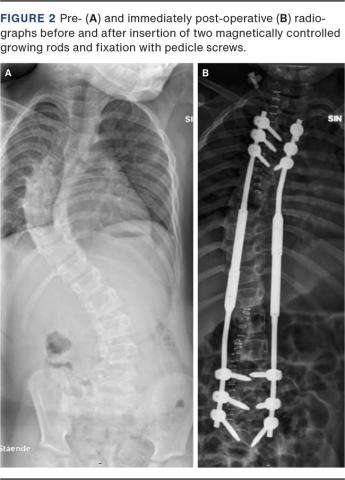

The height from T1-T12 and T1-S1 as well as the Risser Classification were measured on radiographs taken immediately before the primary surgery. The T1-T12 and T1-S1 height were measured again on the latest post-operative radiographs. The spinal height was measured as the perpendicular between two parallel lines passing through the centres of the chosen endplates. The Cobb angle and the thoracic kyphosis angle were measured pre- and immediately post-operatively and again on the latest post-operative radiographs. Rod size, level of instrumented vertebrae and number of anchors were recorded as noted in the procedure description and by analysing the immediate post-operative X-rays. Only the MAGEC system (Nuvasive inc., US) generation 2 was used. Two MCGR and pedicle screws anchors only were used in all cases (Figure 2).

Figure 2